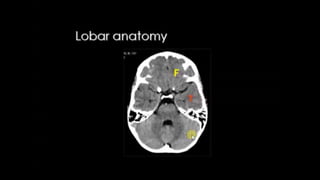

LOBES